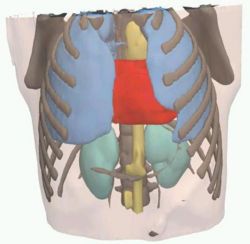

Image Registered FAST (IRFAST) for Combat Casualty Triage

Authors: Kilian Pohl in collaboration with Steve Pieper, Kirby Vosburgh, and Barnabas Takacs.

Background/Purpose: Dr. Pohl's research involves developing an automatic segmentation approach identifying major anatomical compartments from torso CT scans. Using 3D Slicer, he developed a procedure for automatically segmenting the body, bone structures, lungs, and hart from CT images (see figure). The method iterates between the identification of anatomical structures and the registration of an “atlas” to the CT data set of the subject. The atlas is based on CT data set, which we call template, and a label map that already identifies the structures of interest in the template. In the first iteration, the template with the segmentation of the body is mapped onto the CT data set of the subject. This results in a very accurate segmentation of the subject’s body. The method then combines the segmentation of the body and the CT images of the subject to identify the lungs and bone structures. In the second iteration, the method maps the atlas specific label map of body, bones, and lungs to the corresponding label map of the subject. The segmented structures are then used as a "coordinate system" used for the identification of the remaining anatomical compartments.

Grant Support: This work partially supported by SBIR SNC06C0003 TATRC/CIMIT for Image Guided FAST Ultrasound.